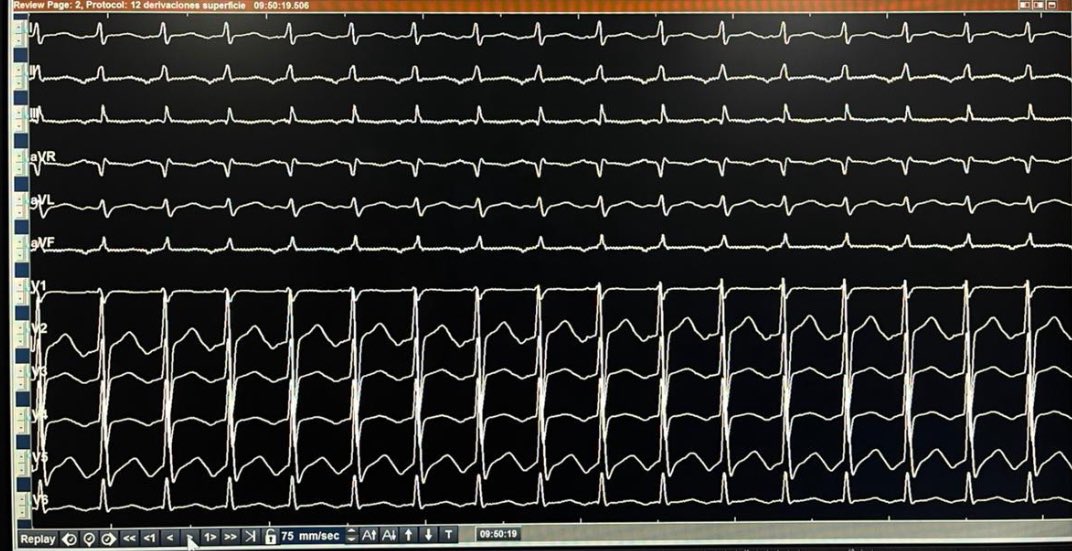

We propose the 5-stage STORM classification for electrical storm – a simple bedside scale that stratifies 30-day mortality from 5% to 50% and helps structure multidisciplinary care